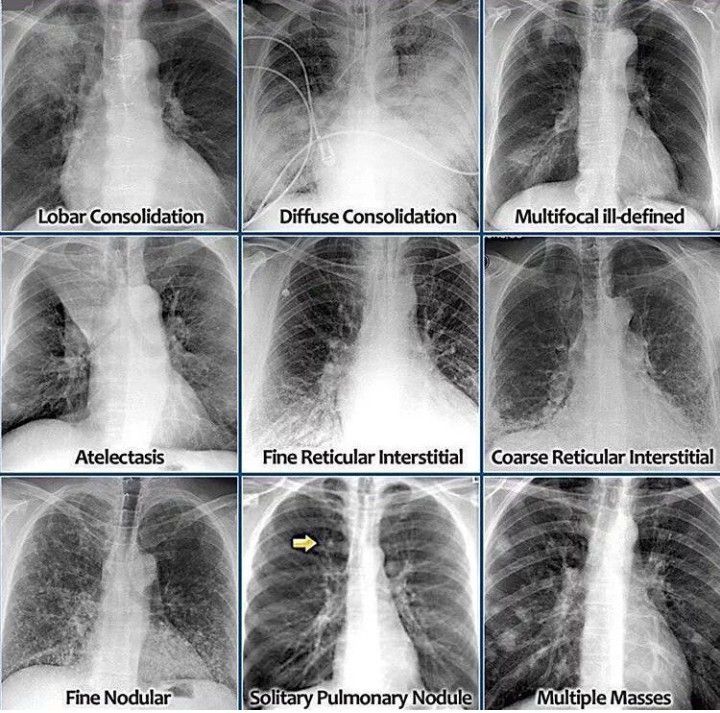

Lung Pathologies on CXR

Here is a pictorial ctoria representation of chest X-ray view of different lungs pathologies .